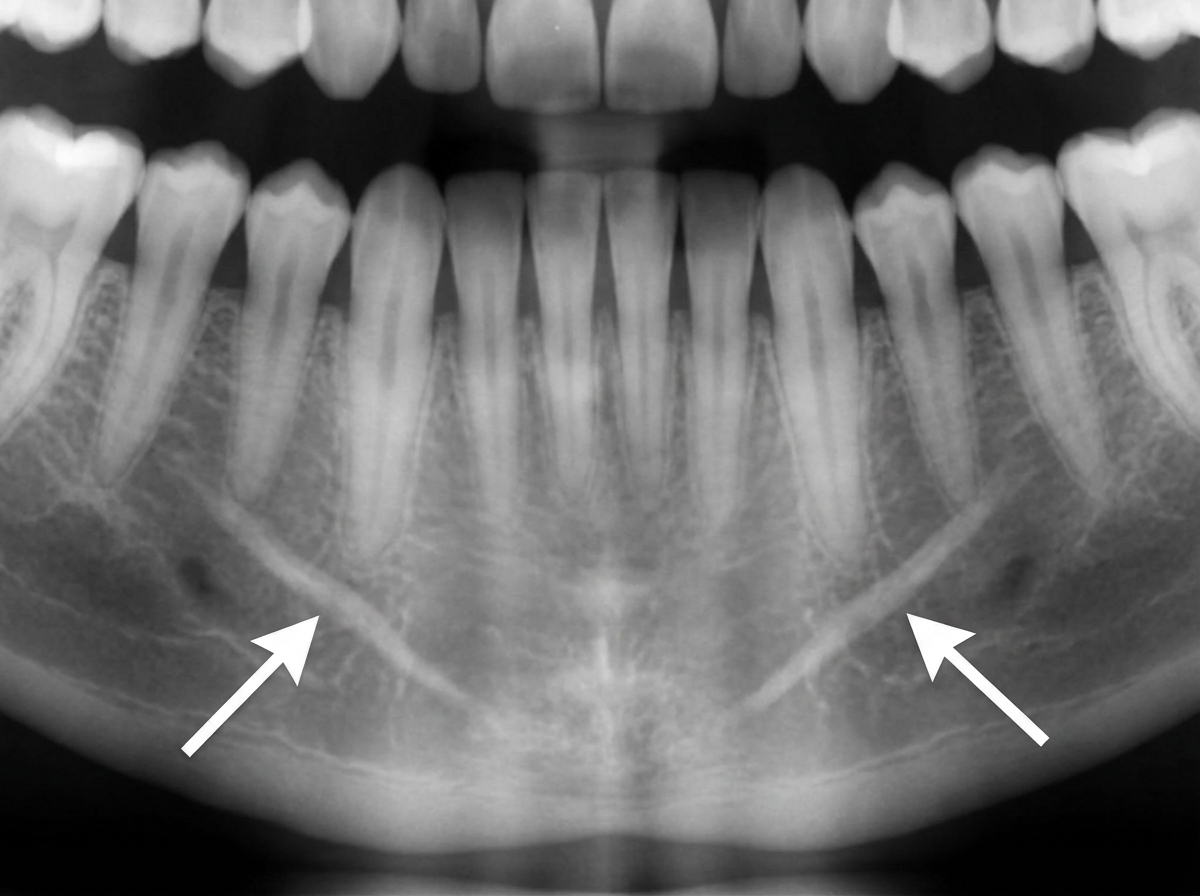

The symmetrical radiopacities marked with arrows are most likely?

Explanation: ***Mental ridges*** - **Bilateral symmetrical radiopacities** on the anterior mandible below the canine-premolar region are characteristic of **mental ridges**, which are bony prominences that provide muscle attachment sites. - They appear as **paired radiopaque lines** running horizontally on either side of the mandibular symphysis and are normal anatomical landmarks. *Genial tubercle* - Appears as a **radiopaque ring or button-like structure** at the **midline symphysis**, not as bilateral symmetrical radiopacities. - Located at the **lingual aspect** of the mandibular symphysis and serves as attachment for **geniohyoid and genioglossus muscles**. *Mylohyoid ridges* - Appear as **oblique radiopaque lines** running posteriorly from the **premolar to molar region**, not as anterior symmetrical structures. - Located on the **lingual surface** of the mandible and provide attachment for the **mylohyoid muscle**. *Both genial tubercle and mental ridges* - **Genial tubercles** appear as a single midline radiopaque structure, not bilateral symmetrical radiopacities as described. - This combination would show different radiographic patterns - a **central ring-like opacity** (genial tubercle) plus **bilateral horizontal ridges** (mental ridges).